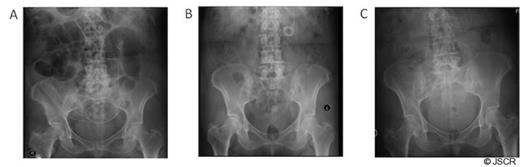

The patient is a 65-year-old-female with a history of recurrent left parietal hemangiopericytoma. One month after embolization and resection of the recurrent hemangiopericytoma, the patient presented with persistent fullness in the left mastoid area. This was significant for a postsurgical residual subgaleal fluid collection. There was concern that this might represent ongoing hydrocephalus. A subgaleal-peritoneal shunt with a Codman Programmable Valve was subsequently placed to decompress the collection and equalize pressure within the area. The subgaleal collection did resolve after shunt insertion. The peri-umbilical abdominal incision was closed in layers, and a tight purse-string was used to close the peritoneum around the distal catheter. Post-operative chest and abdominal radiographs confirmed placement of the shunt tubing over the left hemithorax and the distal shunt catheter within the peritoneum in the left lower quadrant (Fig. 1A).

Distal shunt tip placement. (A) Abdominal radiograph demonstrates placement of the distal shunt tip within the peritoneum immediately post-operatively. (B) Distal shunt tip is shown tightly coiled and overlying the left midabdomen. (C) Distal shunt tip is again confirmed to be intra-peritoneal following distal shunt revision.

Two months later, the patient returned with complaints of headache and visual loss. CT scan of the head showed tumor recurrence in left parietal region, with recurrence of the subgaleal fluid collection, and shunt series showed the distal shunt catheter tightly coiled within the abdomen and overlying the left mid-abdomen (Fig. 1B and 2). The patient was afebrile, the abdomen was soft and non-tender with normal peristalsis and no signs of peritoneal irritation. Because of concern for hydrocephalus, the patient was taken back for distal shunt revision. However, due to the extent of tumor re-growth, the patient was not a candidate for tumor resection. Intra-operatively, the distal shunt catheter was found to have migrated superficial to the rectus sheath, where it had become encapsulated in a pre-peritoneal CSF pseudocyst. The distal portion of the tubing was cut off and new distal tubing was attached with a straight connector. The straight connector was subsequently stitched to the cyst wall to prevent future retraction. Abdominal X-ray reconfirmed peritoneal placement of the distal shunt tip (Fig. 1C).